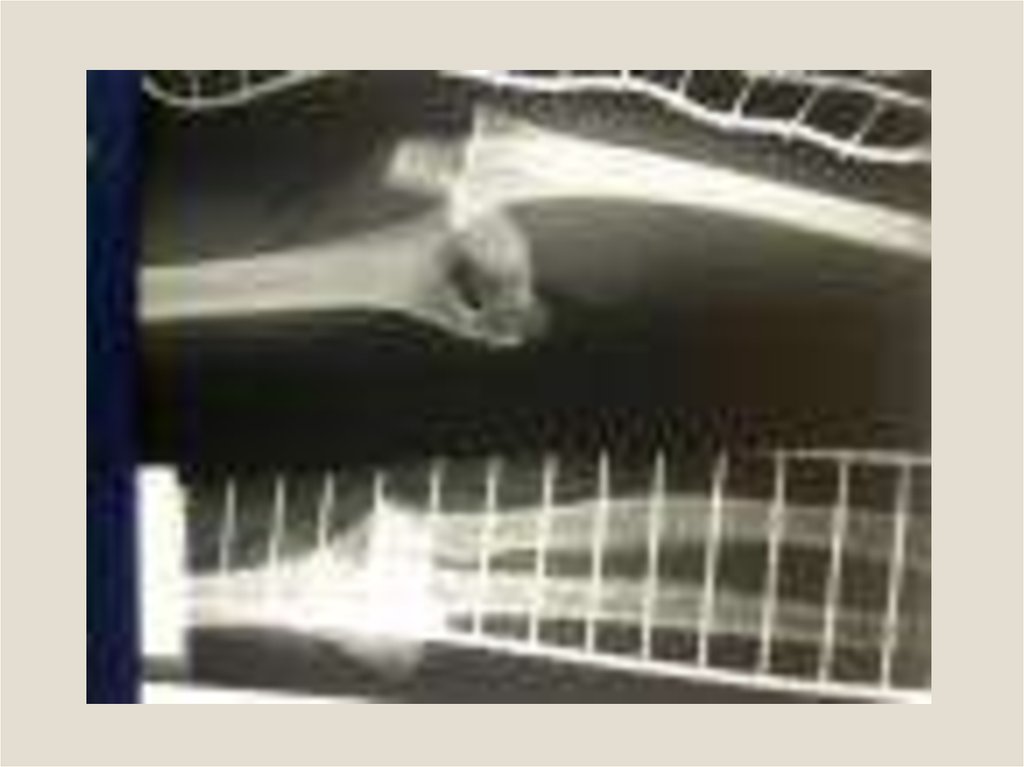

Клиническая анатомия смещения отломков при переломах трубчатых костей. Остеотомия, остеосинтез, пластика трубчатых костей